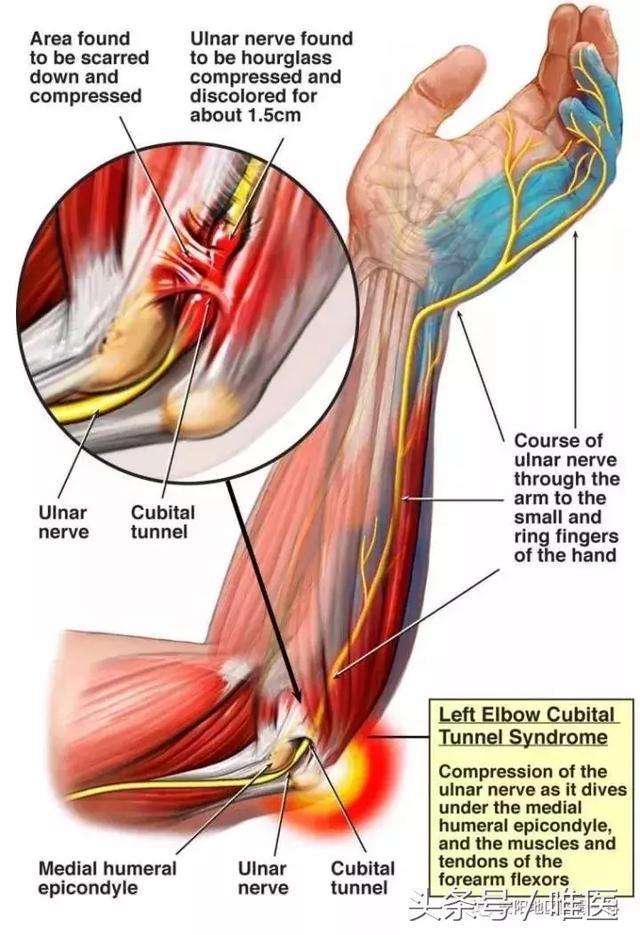

肘管綜合征是僅次於腕管綜合征的第二常見周圍神經卡壓綜合征,又稱遲發型尺神經炎,是尺神經在肘管內受壓引起的環指(尺側)、小指酸痛、麻木,肘部疼痛,手部內在肌肌力下降等症候群的病症。

尺神經起自臂叢神經內側束(C8、T1神經根),在肘部區域,尺神經可受Struthers弓形組織、內側肌間隔、肱三頭肌內側頭、Osborne韌帶、尺側腕屈肌筋膜和深部的尺側腕屈肌腱膜等組織的卡壓。

“哎呦,我去,太專業了!”其實簡單地說,就是尺神經在肘關節處的通道(肘管)變窄了,卡住了,有些“反動勢力”對它進行了壓迫,從而使尺神經不能正常工作並受到損傷。

嚴重者出現手部尺神經支配區域的運動功能障礙、感覺喪失,典型表現是爪形手畸形,因手部小肌肉萎縮而手掌凹陷,掌指關節過伸,指間關節屈曲,因食指、中指的蚓狀肌受正中神經支配,故手指屈曲畸形以環指、小指為著,拇指常處於外展狀態,手指分開、合並動作受限制,小指動作喪失。感覺喪失區主要在手背尺側,小魚際、小指和無名指的尺側一半。